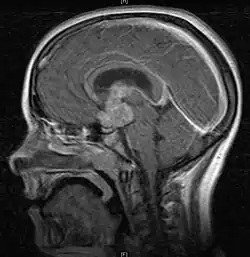

• Mainly located in midline structures, suprasellar region or pineal gland, also basal ganglia and hypothalamus

• Bifocal germinomas (synchronous suprasellar and pineal tumors) regarded as M+ in USA but M0 in Europe

• Toronto; 2006 (1995-2004) PMID 16530340 -- "Limited-field radiation for bifocal germinoma." (Lafay-Cousin L, Int J Radiat Oncol Biol Phys. 2006 Jun 1;65(2):486-92.)

• Retrospective. 6 patients with bifocal germinoma (pineal + suprasellar). All with diabetes insipidus at presentation. Treated with chemo followed by limited-field RT (whole ventricle 24-40 Gy +/- boost). Median F/U 4 years

• Outcome: 100% complete remission

• Conclusion: Bifocal germinoma can be considered locoregional rather than metastatic disease